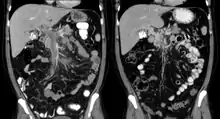

| Portal vein thrombosis seen with computed tomography. | |

The diagnosis of portal vein thrombosis is usually made with imaging confirming a clot in the portal vein; ultrasound is the least invasive method and the addition of Doppler technique shows a filling defect in blood flow. PVT may be classified as either occlusive or nonocclusive based on evidence of blood flow around the clot.[5] An alternative characterization based on site can be made: Type 1 is limited to the main portal vein, Type 2 involves only a portal vein branch (2a, or 2b if both branches are affected), and Type 3 if clot is found throughout both areas.[8] Determination of condition severity may be derived via computed tomography (CT) with contrast, magnetic resonance imaging (MRI), or MR angiography (MRA). Those with chronic PVT may undergo upper endoscopy (esophagogastroduodenoscopy, EGD) to evaluate the presence of concurrent dilated veins (varices) in the stomach or esophagus.[3] Other than perhaps slightly elevated transaminases, laboratory tests to evaluate liver function are typically normal.[1] D-dimer levels in the blood may be elevated as a result of fibrin breakdown.